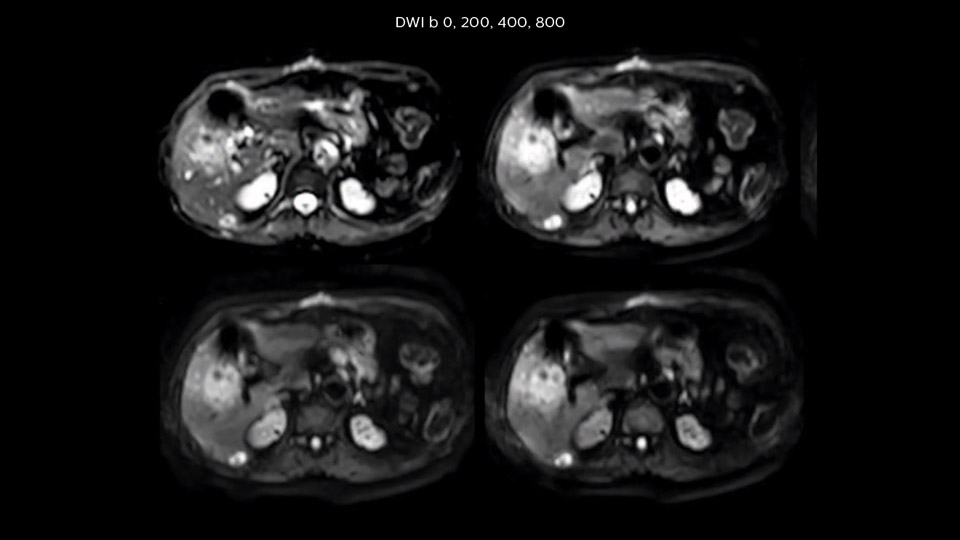

“Our liver exams are quite fast,” says Dr. Baumann. “If the patient tolerates it, we use an arms-up position to reduce the FOV and speed up the exam with dS SENSE.” “We acquire one transversal high resolution T2-weighted sequence with 3 mm slice thickness, for example for pancreas or liver lesions. Then we also add a T2 fat suppressed MultiVane XD SPIR sequence. We perform these two routinely in our liver imaging. We use high dS SENSE factors to significantly shorten scan times to 2-4 minutes, which can improve our protocol; it’s a very robust scan.” “We include mDIXON for the dynamic sequences because of the robust and homogeneous fat suppression we get with that. We had been using eTHRIVE, but we are now quite happy with mDIXON. Sometimes we use a medication to calm the bowels, to further improve the image quality.”

Dr. Baumann then implemented MultiVane XD for motion correction. It uses an extended reconstruction algorithm for imaging that is virtually motion free. “With MultiVane XD we get excellent motion-corrected images with high spatial resolution. We typically first optimize our scan for high image quality, and when satisfied with that, we try to reduce the scan time. So, we combined MultiVane XD with dS SENSE, which allows us to shorten the scan time,” he explains. “The performance of MultiVane XD in liver imaging is outstanding. MultiVane XD with dS SENSE is a powerful development in improving liver image quality.” “As we use breathhold imaging for T2-weighted liver scans, we depend on the patient’s ability to cooperate with the exam. This can present a real challenge when we are looking for small lesions, such as in our oncological patients. However, with MultiVane XD motion correction, we get excellent images. This is important for our surgeons, because they want to know exactly where the lesions are.”